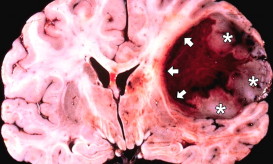

Σημαντική αύξηση του προσδόκιμου ζωής σε ασθενείς με καρκίνο εγκεφάλου (γλοίωμα βαθμού IV) δίνει πρωτοποριακή συνδυαστική θεραπεία!